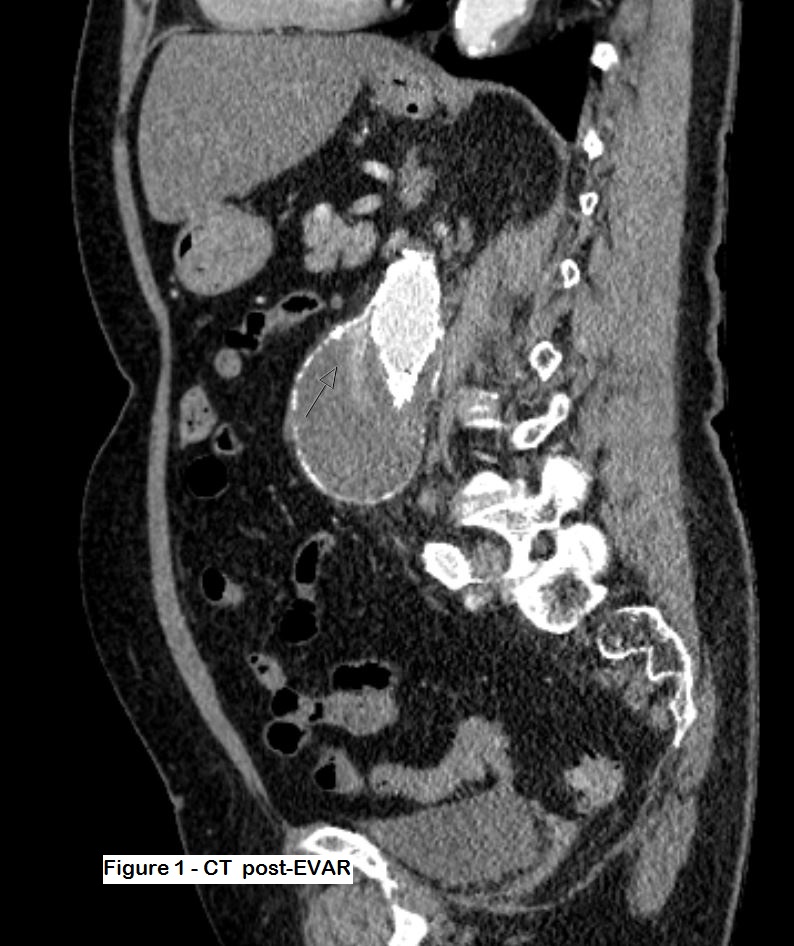

Figures 1 and 2: Post-op CT which shows some contrast within the aneurysm sac but it is difficult to ascertain the type of leak. The patient was thus referred for an ultrasound study.